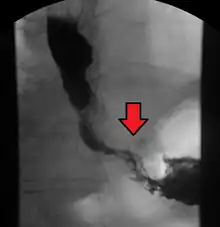

Although an occlusive tumor may be suspected on a barium swallow or barium meal, the diagnosis is best made with an examination using an endoscope. This involves the passing of a flexible tube with a light and camera down the esophagus and examining the wall, and is called an esophagogastroduodenoscopy. Biopsies taken of suspicious lesions are then examined histologically for signs of malignancy.

Additional testing is needed to assess how much the cancer has spread (see #Staging, below). Computed tomography (CT) of the chest, abdomen and pelvis can evaluate whether the cancer has spread to adjacent tissues or distant organs (especially liver and lymph nodes). The sensitivity of a CT scan is limited by its ability to detect masses (e.g. enlarged lymph nodes or involved organs) generally larger than 1 cm.[41][42] Positron emission tomography is also used to estimate the extent of the disease and is regarded as more precise than CT alone.[43] Esophageal endoscopic ultrasound can provide staging information regarding the level of tumor invasion, and possible spread to regional lymph nodes.

The location of the tumor is generally measured by the distance from the teeth. The esophagus (25 cm or 10 in long) is commonly divided into three parts for purposes of determining the location. Adenocarcinomas tend to occur nearer the stomach and squamous cell carcinomas nearer the throat, but either may arise anywhere in the esophagus.